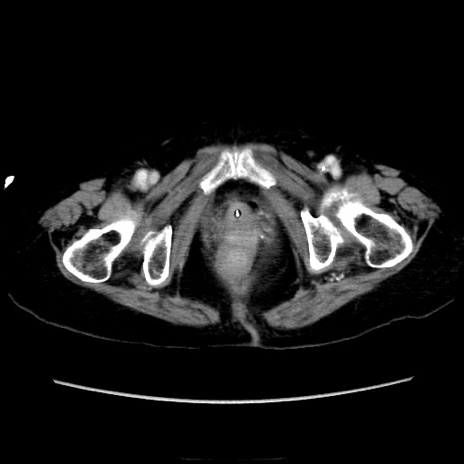

症例40(横断像)

横断像